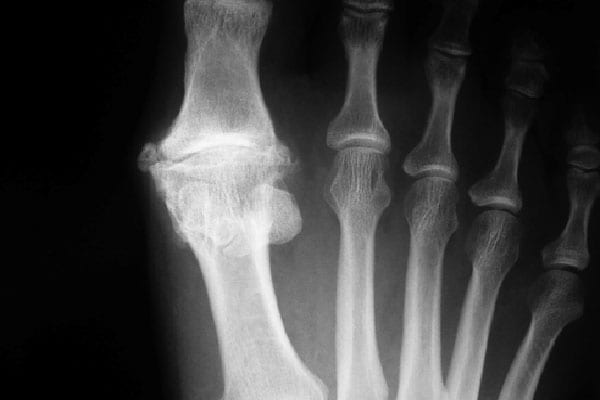

Чаще всего такое воспаление большого пальца ноги диагностируется у мужчин после 40 лет, хотя может проявляться и раньше. Причиной развития патологии становится повышенный уровень мочевой кислоты, которая преобразуется в соль и откладывается между косточками суставов. Именно эти отложения провоцируют развитие болезненного процесса.

Что касается симптомов, то они таковы: сильные болевые ощущения, которые проявляются преимущественно в ночное время; появление отечности и повышение местной температуры на пораженной области. Кроме того, может повышаться общая температура тела.

В некоторых случаях для лечения подагры большого пальца ноги приходится прибегать к хирургическому вмешательству. Но эта процедура применяется только в том случае, если консервативное лечение не дало положительного результата, а функции сустава ограничены из-за остеофитов (костных наростов).

Операция предусматривает вырезание нароста или удаление пораженного сустава.